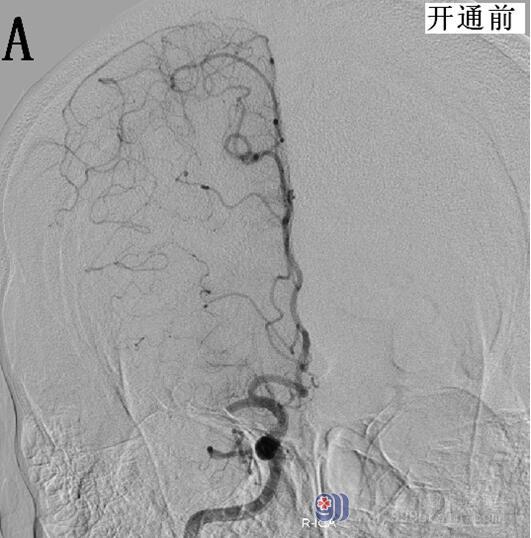

结合患者病史及查体评估,具有静脉溶栓指征,无禁忌症。请示王展航科主任后建议rt-PA静脉溶栓治疗,溶栓后桥接脑血管造影评估血管情况。告知患者家属病情,家属知情并同意溶栓及介入治疗。19:48开始使用rt-PA(50mg),15分钟后患者症状改善,左下肢肌力3+级,双侧眼球左侧活动稍受限,双眼右向凝视,构音欠清,左侧肢体肌力0级,右侧肢体肌力5级,伸舌左偏,左下肢病理征(+),NIHSS评分10分。20:15推入DSA室,行脑血管造影显示右侧大脑中动脉仍存在闭塞,立即桥接取栓+支架置入治疗,约22:30手术结束,术后大脑中动脉上干开通,血流速度恢复,大脑中动脉下干远端闭塞,但大脑前动脉可部分代偿,患者安返病房,生命体征平稳,复测患者NIHSS为6分,溶栓及桥接治疗有效(图2)。复查头部CT,明确无再通后出血,维持血压,预防患者再灌注损伤,定期评估患者NIHSS评分,密切关注生命体征,24小时后启动抗血小板治疗。8天后患者病情明显好转,肢体已恢复部分活动,可自行行走,查体仅遗留左侧肢体肌力5-级,余神经科查体无明显阳性体征。NIHSS:2分。请示王展航科主任,可予带药出院,嘱低盐低脂饮食,戒烟戒酒,控制血压。

图2 A、B为开通前的脑血管造影;C、D为脑血管开通后的造影显像